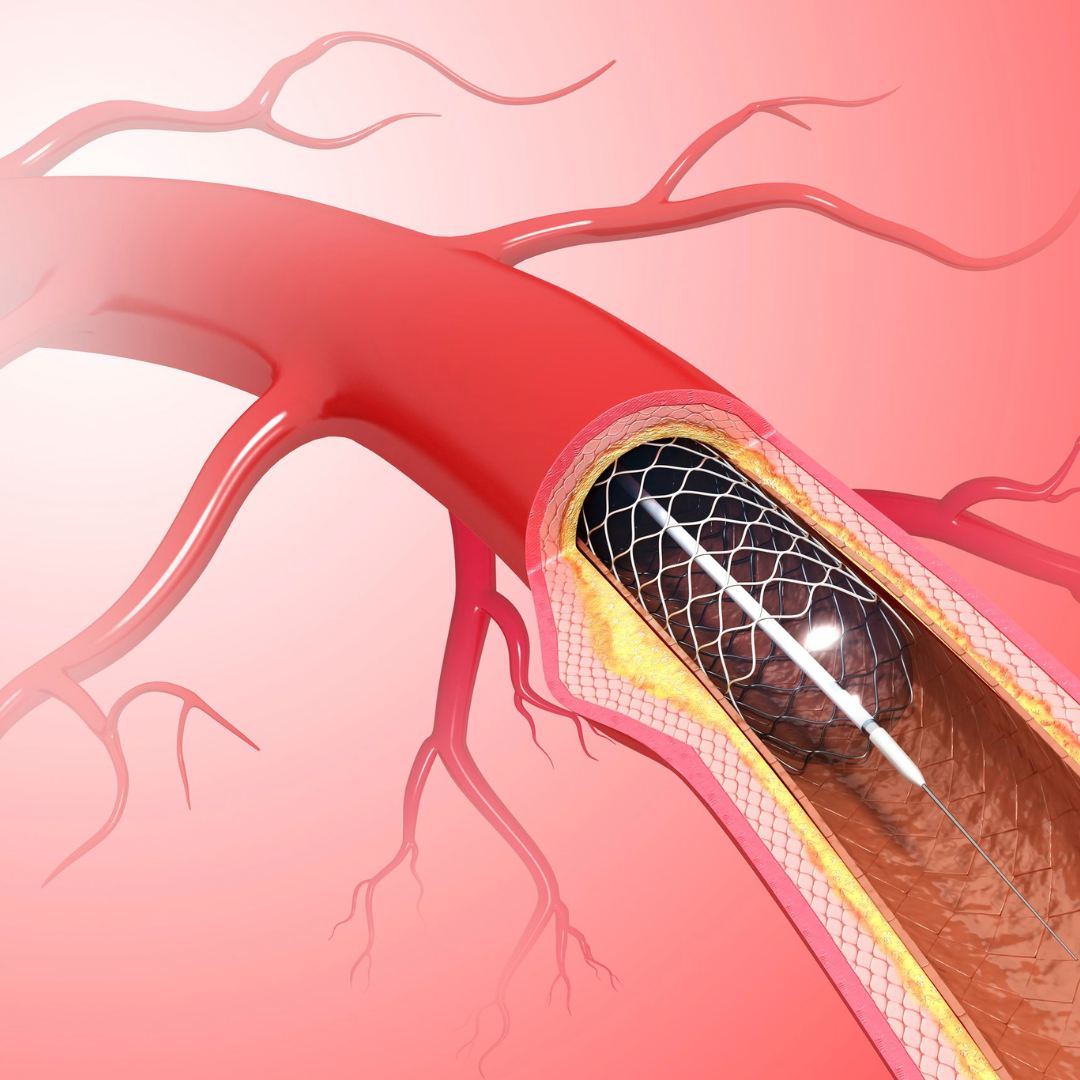

Angioplasty (Stent)

A minimally invasive procedure where a balloon and stent are used to open blocked heart arteries and restore proper blood flow.